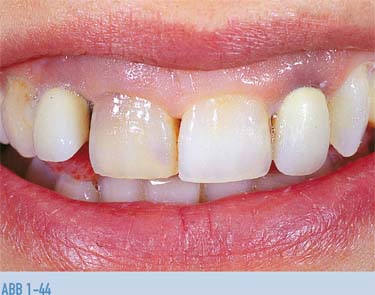

Abb. 1-43 31-jährige Frau mit Metallkeramikkronen auf den devitalen seitlichen Schneidezähnen im Oberkiefer; rötlich braune Verfärbung des rechten zentralen Schneidezahnes, der zehn Jahre zuvor devitalisiert worden war. Kurze Oberlippe, dadurch Gingivaexposition beim Lächeln. Diese Befunde und die unterschiedlichen Farben machen das Lächeln deutlich unästhetisch.

Abb. 1-44 Stärkere Vergrößerung der Frontzahnregion. Nach der Vorbehandlung mit zwei Sätzen an Provisorien entschied man sich für zwei Keramikkronen auf die seitlichen Schneidezähne und für Keramikveneers auf die zentralen Schneidezähne. Ziel ist es, den überbiss durch Kürzen und Verändern der Form der Zähne zu korrigieren, wie im Waxup (Abb. 1-48) zu sehen. Gleichzeitig sieht der Behandlungsplan vor, die Kronen zu verlängern und den Zenit der Gingiva in eine idealere Position zu verlagern sowie durch Verlagerung der Gingiva auf Höhe der Schmelz-Zement-Grenze die gesamte klinische Krone freizulegen. Unter Beibehaltung der okklusalen Führung reduziert dies den überbiss und das „gummy smile“.